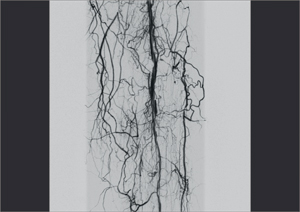

— Субстракционная ангиография

Ziehm Vision RFD - уникальный мобильный рентгеновский аппарат с возможностью многостороннего клинического применения. Плоскопанельный детектор аппарата дает отличные высокоточные изображения, обеспечивая прекрасную визуализацию для инвазивной радиологии, нейрохирургии, сосудистой хирургии, кардиологии и при инвазивных процедурах, таких как аневризма абдоминальной аорты или ЧТКА, и находит также применение в гибридных областях,

как например, при имплантации аортального сердечного клапана.

Компания Ziehm Imaging впервые предоставила возможность использовать все достоинства плоскопанельных детекторов в мобильных установках. Благодаря плоскому детектору 30 х 30 см область видимого поля увеличилась в 2.5 раза по сравнению с обычным усилителем изображения 23 см. Отсутствие S-образной дисторсии, широкий динамический диапазон и превосходное отображение всех анатомических деталей делает этот аппарат идеальным выбором для широкого спектра клинических процедур.

Ziehm Vision RFD - уникальный мобильный рентген с плокопанельным детектором для многостороннего клинического применения. Аппарат дает отличные высокоточные результаты в инвазивной радиологии, нейрохирургии, сосудистой хирургии, кардиологии и при инвазивных процедурах, таких как аневризма абдоминальной аорты или ЧТКА, и находит также применение в гибридных областях, как например, при имплантации аортального сердечного клапана. Специальный программный пакет SmartVascular позволяет выполнять цифровую субтракционную ангиографию, в том числе с возможностью использования CO2 как контрастного вещества. Возможность установки дополнительных потолочных мониторов и внешнего интерфейса управления, а так же расширенное орбитальное вращение штатива делают Ziehm Vision RFD незаменимым аппаратом для многофункциональных операционных.

• Программный пакет для сосудистой хирургии: DSA, MSA, RSA и CО2